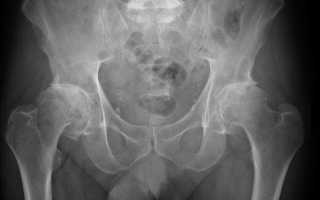

В тазовой области есть вертлужная впадина, в которой помещается головка шейки бедра. Их укрывает хрящевой покров, который предназначен, чтоб амортизировать движения и не давать костям биться друг об друга. Недостатком хрящей является отсутствие в них нервных окончаний, которые могли бы предупредить организм о чрезмерных нагрузках. Но вместо этого, ткань понемногу разрыхляется и изменяет свои свойства, теряя при этом возможность выполнять прямые функции.

В щелях, которые есть в суставе, присутствует синовиальная жидкость, напоминающая белок яйца. Она осуществляет все жизненные обменные процессы и служит неким смазочным материалом для хряща. Во время разряжения хрящевой ткани, частички попадают в синовиальную жидкость, впоследствии проникая в оболочку и капсулу сустава. Происходит воспаление и ухудшение качества выделяемой жидкости. Головка начинает покрываться остеофитами, которые и становятся причиной болевых ощущений при ходьбе.

Первое и самое эффективное, что могут назначить врачи в качестве обследования это магнитно-резонансная томография. На сегодняшний момент это самый эффективный метод диагностирования, так как объемное качественное изображение наилучшим образом может передать степень разрушения. А именно в это время наблюдается значительное увеличение деформации головки кости и ее контуров, сужение суставной щели и значительное увеличение остеофитов.

На третьей стадии наблюдается сильная атрофия мышц, так как пациент уже не в состоянии наступать на поврежденную конечность. Боли становятся непрекращающимися и доставляют многочисленные страдания пациенту. Походка начинает напоминать утиную из-за перекоса бедра, которое, в свою очередь, подверглось сильным изменениям. Суставная щель практически исчезла или так сужена, что ее сложно разглядеть на рентгеновском снимке. Без защиты гиалинового хряща, кости подвергаются наиболее сильным трениям, которым значительно мешают возникшее большое количество остеофитов.